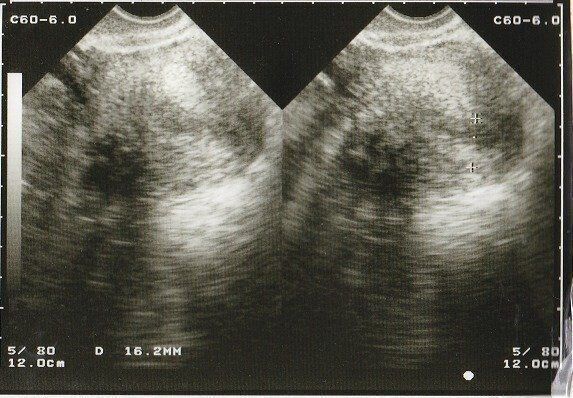

くろみつさんの妊娠4週目のエコー写真 直径9mmの小さな、小さな胎嚢を確認

妊娠検査薬で陽性反応が出たので、夫が休みの週末を待って2人で病院へ行きました。左上部に見える黒い丸が妊娠した目印となる胎嚢です。「やっと妊娠できた」という、うれしさはもちろんありましたが、小さな命が自分のおなかの中にあるということが信じられず、他人事のような不思議な感覚でした。